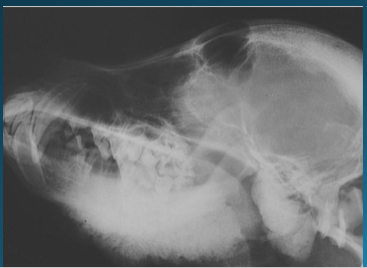

Craniomandibular osteopathy

Increased deposition of new bone along the mandible in puppies